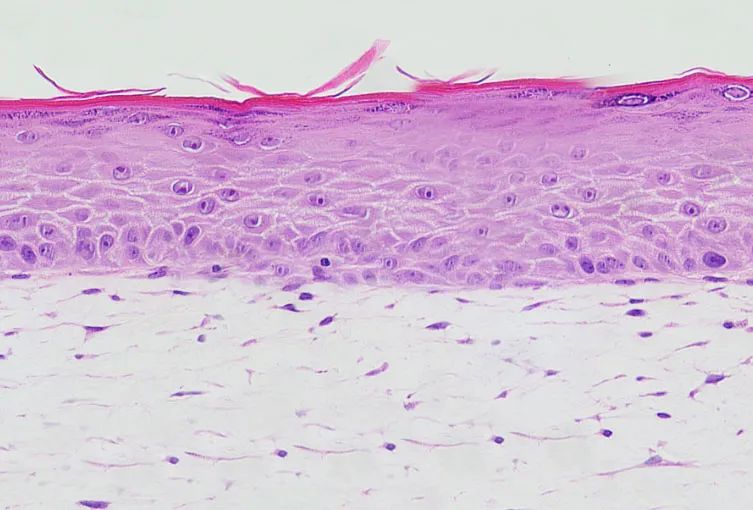

3D全層皮膚模型

3D全層皮膚模型除了含表皮層外,還包括成纖維細胞構(gòu)建的真皮層,基本模擬了人體皮膚的“全層”。

利用組織工程技術(shù)構(gòu)建全層模型的過程通常如下:將活體的成纖維細胞在支架上培養(yǎng)形成真皮結(jié)構(gòu),再進一步與角質(zhì)形成細胞進行復合培養(yǎng)形成全層結(jié)構(gòu)。和人體皮膚一致的是,全層皮膚模型具備充分的真皮-表皮細胞相互作用。

目前已有多款3D全層皮膚模型在體外構(gòu)建成功:其中包括法國的T-Skin、美國的EpiDerm FT、德國的Phenion FT以及中國的FulKutis 。

圖:FulKutis 全層皮膚模型,圖源博溪生物官網(wǎng)